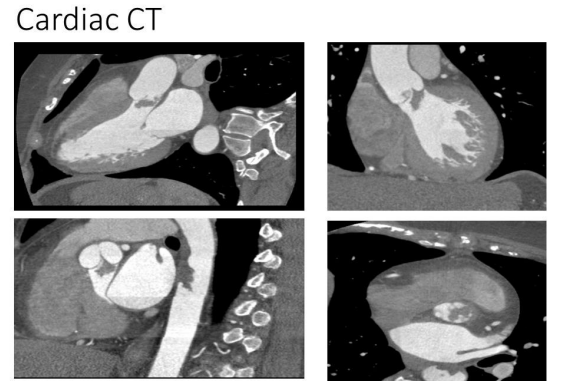

Cardiac CT Findings

Cardiac CT confirmed:

• A 1.6 cm × 1.19 cm aortic valve mass between the left and right coronary cusps, extending into the LVOT

• A normal aortic root and ascending aorta

• A pedunculated lesion within the descending aorta, measuring 1.4 cm × 1.2 cm × 4 cm

Figure 2